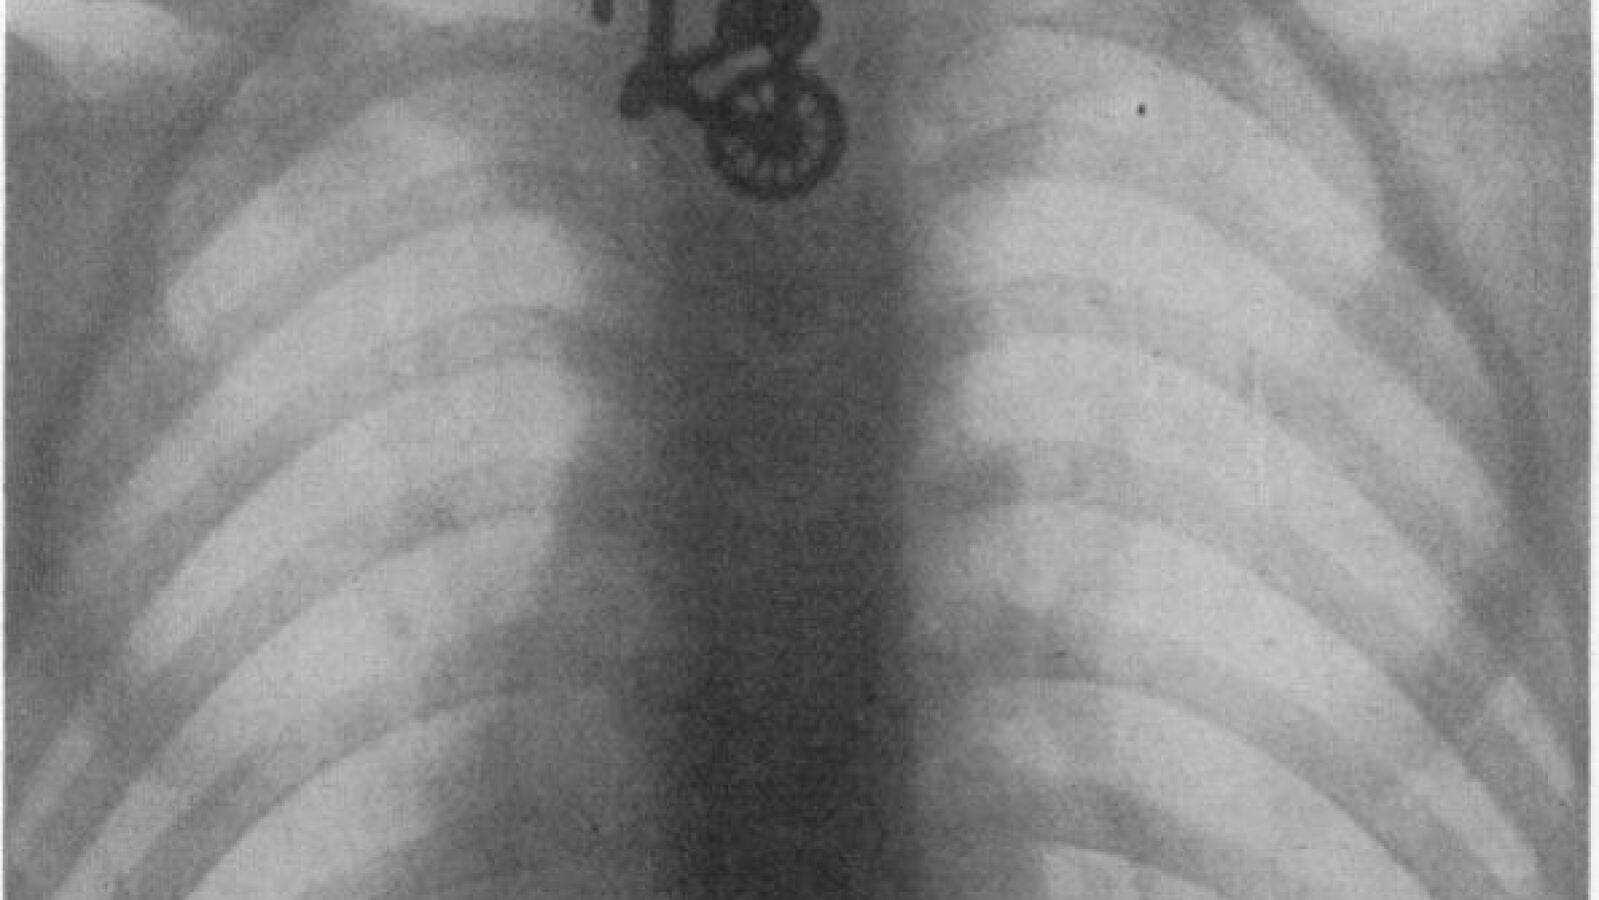

Entre lo más inaudito está una radiografía del esófago de un niño que se tragó una bicicleta de juguete en 1906 o el chaval de ocho años, diagnosticado con hiperactividad, que se tragó durante meses los perdigones de los gansos que cazaba y comía su familia como parte de un juego con su hermano.